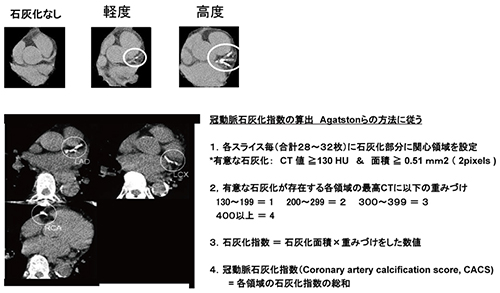

Amazon.com: CT冠動脈造影実践学: 9784498013568: unknown, 冠動脈CTによる狭心症の診断,

冠動脈CTによる狭心症の診断, 沖縄県医師会_沖縄県医師会報(2013年3月号),

沖縄県医師会_沖縄県医師会報(2013年3月号), 放射線 CT - 榊原記念病院,

CT装置|徳島赤十字病院, 320列面検出器CTによる新しい冠動脈CT技術 吉岡邦浩(岩手医科,